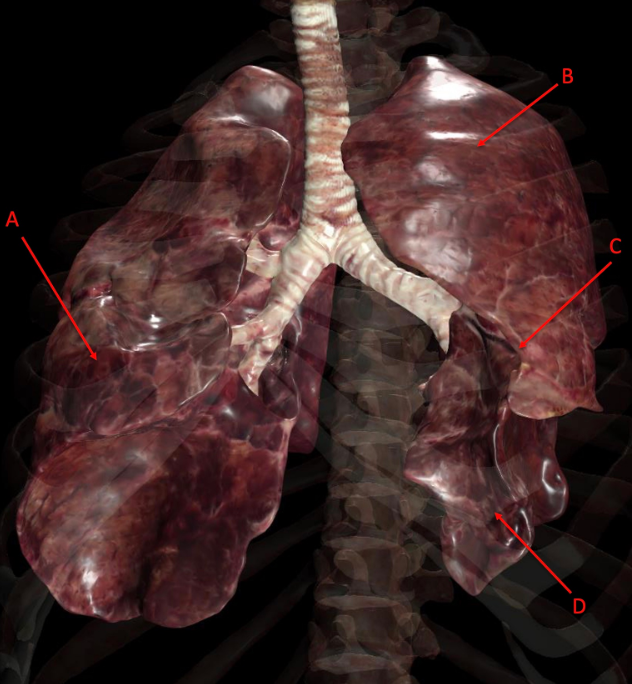

Identify the following structure(s)

A

A. right middle lobe

B. left superior lobe

C. cardiac notch

D. left inferior lobe